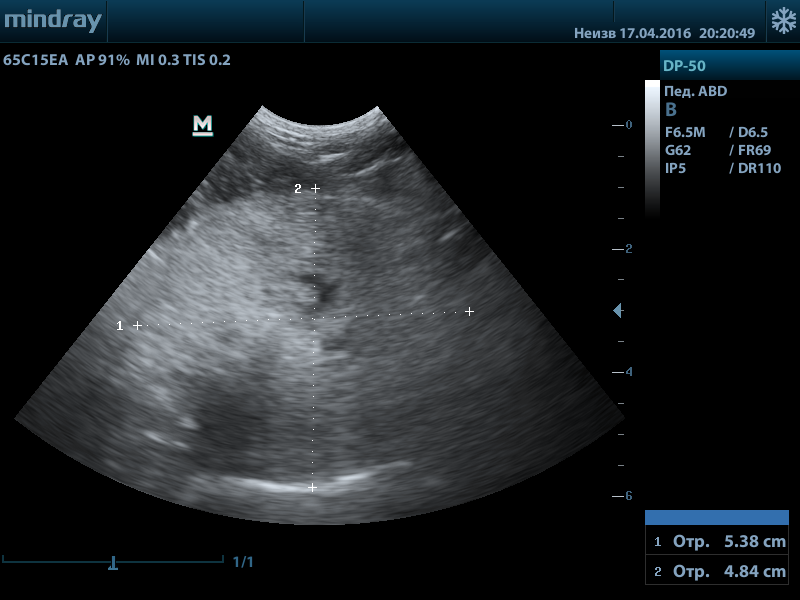

В норме при УЗИ предстательная железа с четким ровным контуром, однородная, зернистая, без патологических образований. Простатическая часть уретры не расширена. Доли симметричные, округлые. Нормальные размеры предстательной железы у кобелей 2-4см.